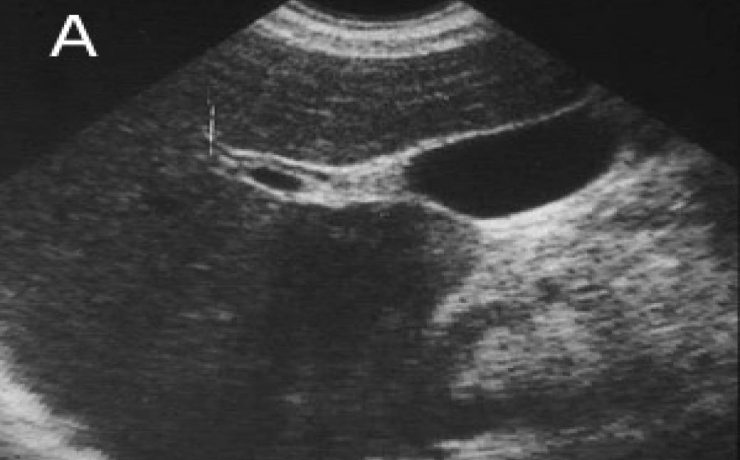

La incidencia de coledocolitiasis después de la intervención quirúrgica tiene una incidencia del 10 porciento, Los cálculos pueden permanecer por años dentro de la vía extra hepática y no manifestar síntomas. Los cálculos pequeños pueden pasar por el colédoco y el duodeno sin producir síntomas (menores 3mm), solo que se